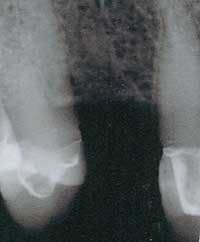

Figure 3 - Preop radiograph. Excellent bone present.